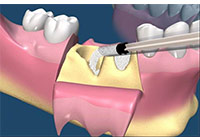

上顎犬齒是牙齒萌發順序最晚的牙齒,加上它萌發的路徑較其他牙齒長,這也造成上顎犬齒是上顎最常見的阻生牙。女性的好發率也高於男性。上顎機率高於下顎。診斷出上顎犬齒阻生需要靠臨床觀察與影像學判斷。在影像學方面,根尖片雖然是一個二維的影像,但是可以顯示牙齒與鄰牙間的相對關係。而確切的位置評估則需要藉由電腦斷層來定位。如果較晚發現犬齒已異位萌發,則可以藉助翻辫瓣手術將矯正器黏在犬齒,並用矯正力量拉下犬齒。 (圖05-08)

圖8